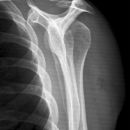

Schulter axial

Beurteilungskriterien